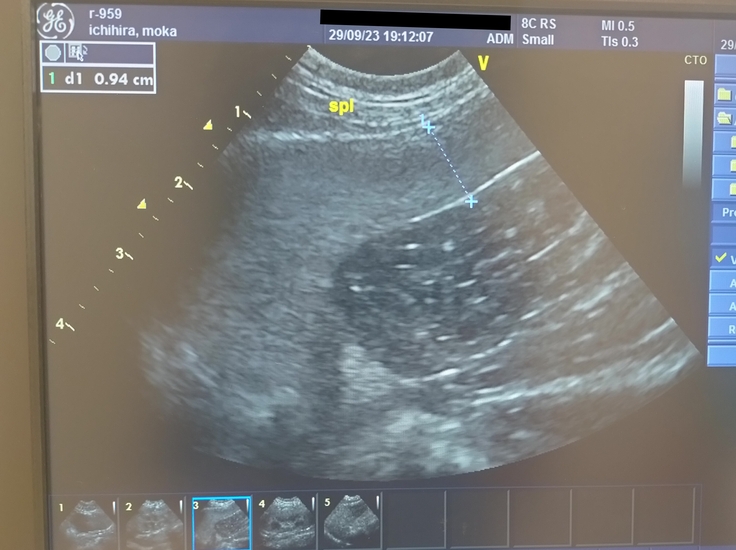

エコー検査の結果、腎臓、肝臓、脾臓、膀胱、そしてリンパ腫が出来ていた腸もどこも異常はなく綺麗で、無事寛解維持😭👏👏

ちなみに…脾臓がちょっと大きいらしいのですが、元々かなぁ?とのことでした!(大型猫なので🐱薄い子は0.5cm~!モカは約1cmです)

脾臓は古くなった血球を処分したり、血を蓄える機能があるそうで、抗がん剤治療をしているとパンパンに腫れることもあるらしく、それの名残りも0ではないようですが、

全く病的な範囲ではないし問題ないですよ~と!!👩⚕️よかったε-(´∀`;)ホッ